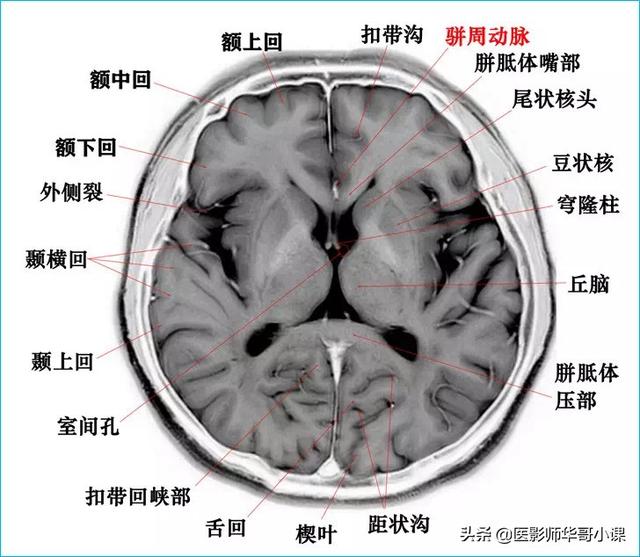

颅脑主要包括大脑、小脑、脑干、间脑,其中大脑又称为端脑,是人体的司令部,管辖人体的躯体活动、精神活动以及感觉行为等;脑干和小脑位于后颅窝的位置,脑干自上而下分为中脑、脑桥、延髓,脑干又称为生命中枢,对人体非常重要,因为脑干具有管辖呼吸和循环的初级生命中枢。其中大脑分为5个脑叶,分别是额叶、顶叶、颞叶、枕叶以及内侧面的岛叶。间脑分为上丘脑、下丘脑、后丘脑、背侧丘脑和底丘脑,背侧丘脑是一个重要的结构,是感觉传导路的重要中继站。颅脑包括颅骨和颅骨内的脑组织。颅骨由顶骨,颞骨,枕骨,额骨,以及颅底骨构成。颅骨构成的颅腔主要作用是保护脑组织。颅内的脑组织主要包括大脑,小脑,脑干。表面覆盖有软脑膜和硬脑膜,大脑分为左右两侧大脑半球,根据解剖位置又分为颞叶,枕叶,顶叶,额叶,各脑叶功能不尽相同。小脑也分左右半球。脑干分为延髓,脑桥和中脑三部分。

颅脑磁共振可提供冠状位、矢状位和横位三维的图像,图像清晰度高,对人体没有放射性的损害,尤其是可以清楚的显示脑干、小脑及后颅窝的病变,颅脑磁共振平扫可以用于诊断脑梗死、脑炎、脑肿瘤、颅脑先天发育畸形、颅脑外伤等。